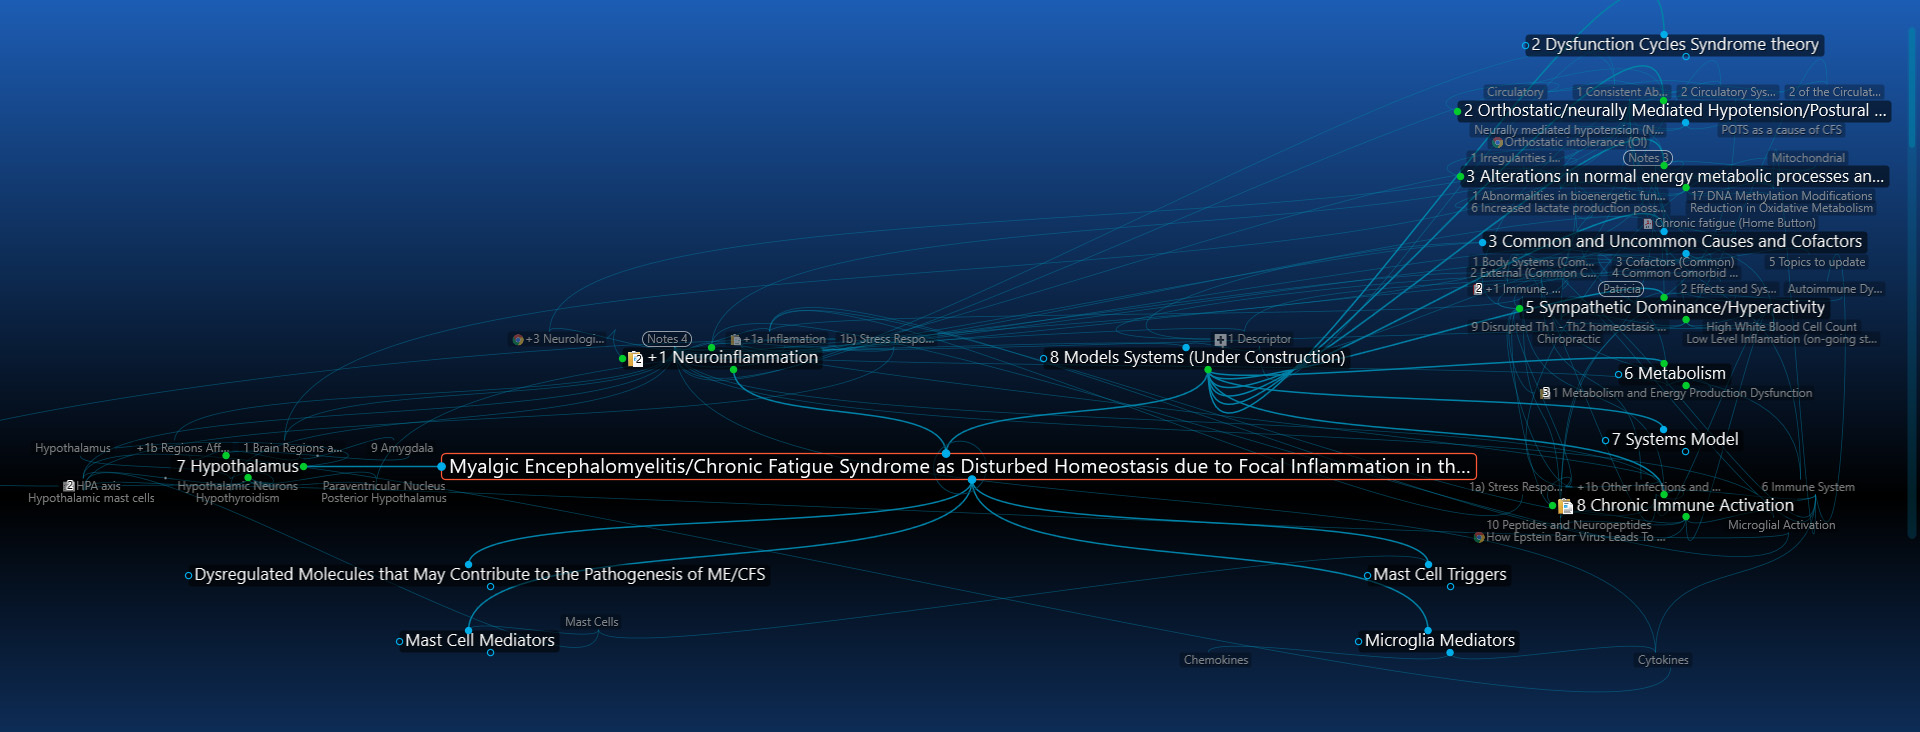

8) Hypothalamus